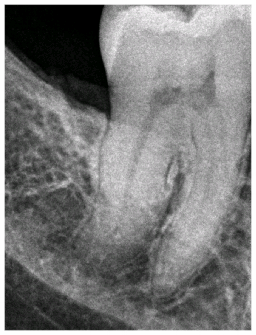

Before After

Before and after X-rays demonstrating a healthy bony refill on the distal of the lower molar after only one session of Perioscopy. Bone loss on the back of the last molar is a common problem occurring after extraction of some wisdom teeth. With the help of Perioscopy we can now save more teeth than ever before!